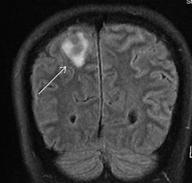

• Contrast MRI brain:Suspected diffuse supratentorial leptomeningeal enhancement and nodular thickening.

• CSF shows involvement by plasma cell myeloma

• Managed as isolated CNS relapse

CNS relapse (leptomeningeal disease) while on teclistamab 11/2024

MRI brain (6/2025):

- Leptomeningeal enhancement are detected at bilateral parasagittal and bilateral cerebral hemispheres.

- Multiple focal enhancing cerebral lesions have been detected, most likely indicative of brain metastasis. These are associated with perilesional vasogenic edema.